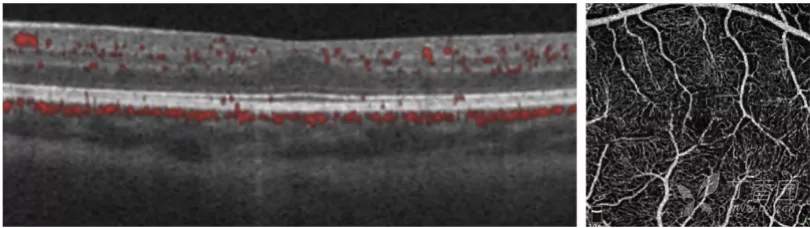

急性ROP4期OCT图像

图. 4A期视网膜脱离:OCT可见中心凹视网膜附着(星号),视网膜内渗出(高反射点)、周边部视网膜脱离和视网膜劈裂。

图. 4B期视网膜脱离:OCT可见中心凹视网膜脱离(星号),在检眼镜检查中很难识别。